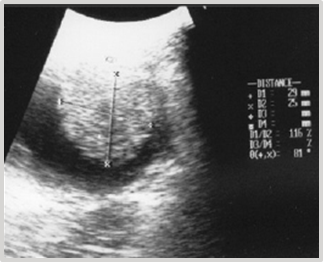

The patient, a 9-year-old female Great Dane canine, presents with intermittent clinical signs of cystitis. Urine culture confirms its bacterial origin. The established antibiotic therapy is ineffective. The diagnosis is reconsidered. The ultrasound report indicates the presence of two closely spaced hyperechoic images, one measuring 1.61 cm x 1.16 cm and the other measuring 1.40 cm x 1.08 cm, implanted in the dorsal wall of the fundus of the urinary bladder. They involve 1/3 of its thickness (Figure 19). A laparotomy and cystotomy are performed, and the tumor is exposed through the ventral surface of the bladder using the "glove finger" maneuver.

Figure 19 Ultrasonographic Image: 2 closely spaced, hyperechoic masses in the bladder measuring 1.61 cm x 1.16 cm and 1.40 cm x 1.08 cm.